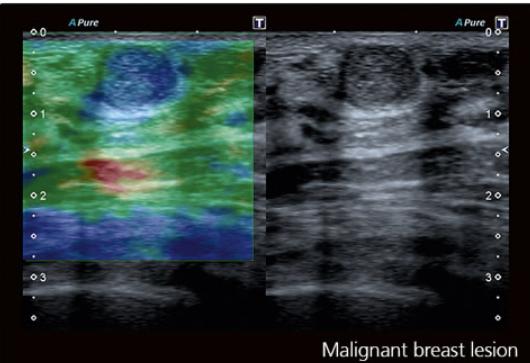

ԿՐԾՔԱԳԵՂՁԻ ԷԼԱՍՏՈԳՐԱՖԻԱ